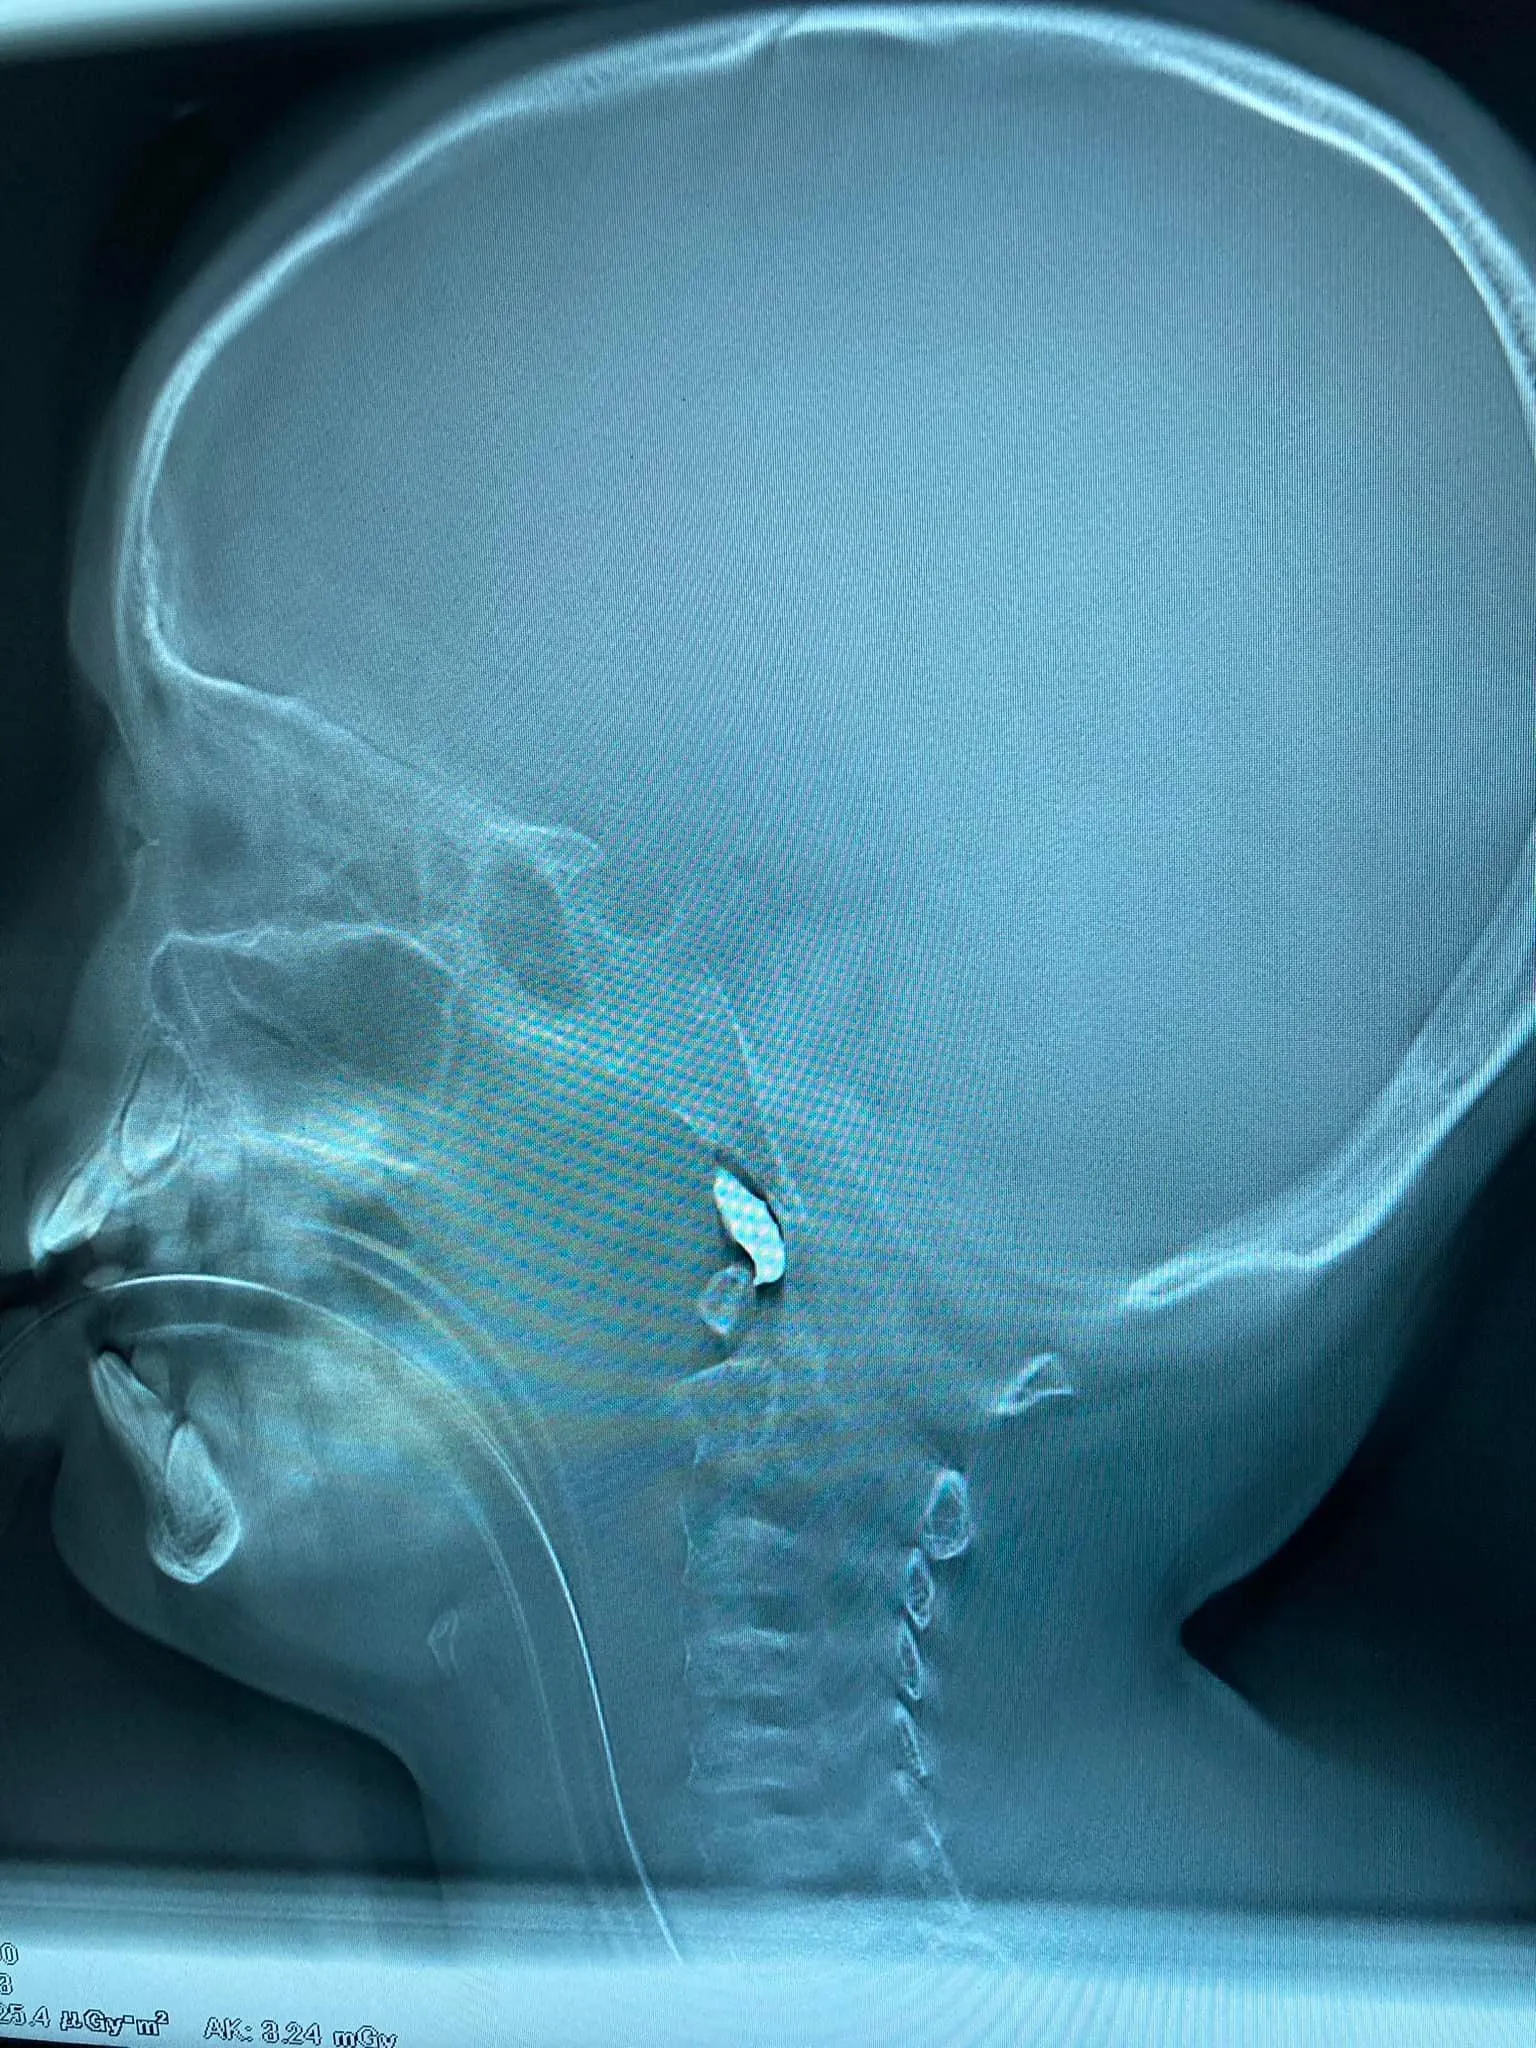

В комментариях к сообщению он добавил, что осколок вошел через скулу. Локализация – очень сложная, но ключевые артерии не задело.

Осколок вошел через скулу / Фото Духновского